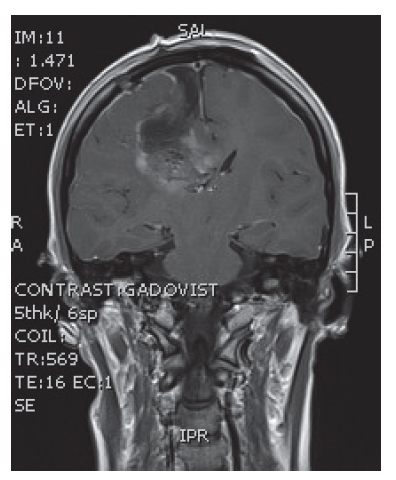

V naší kazuistice prezentujeme 25letou pacientku s negativní onkologickou rodinnou anamnézou, která dosud vážněji nestonala. Udávala asi 3 měsíce progredující bolesti hlavy a krční páteře, zvracení, postupně rozmazané vidění a parestezie horních končetin. Byla provedena magnetická rezonance, na které diagnostikován tumor mozku ve frontálním laloku vpravo, vyplňující frontální roh postranní komory velikosti 6x5 cm, midline shift, mass efekt. Dne 23. 9. 2013 ji byla na neurochirurgické klinice provedena neradikální exstirpace tumoru z parasagitální kraniotomie. Histologicky byl prokázán glioblastom multiforme gr. IV. Od 30. 10. 2013 do 12. 12. 2013 absolvovala konkomitantní radiochemoterapii (radioterapie do CLD 60,0 Gy) s temozolomidem (75 mg/m2 per os D1-42). Od ledna do dubna 2014 pokračovala v chemoterapii temozolomid solo v dávce 150 mg/m2, resp. od 2. cyklu 200 mg/m2 D1-5 ( Temodal tbl, celkem 4x). Na kontrolní MRI mozku ze dne 20. 5. 2014 byla prokázána progrese rezidua. Dne 4. 6. 2014 podstoupila druhou operaci, histologicky verifikován glioblastom multiforme s přechodem v gliosarkom. Snažili jsme se získat informace ze zahraniční literatury s léčbou gliosarkomu, bohužel se jedná o velmi vzácné onemocnění a údajů není mnoho. Nakonec byla zvolena léčba podle protokolu ICE (ifosfamid, carboplatina, etoposid), který je obdobou režimu PEI. Dávky: ifosfamid 1000 mg/m2 D1-3, carboplatina 110 mg/m2 D1 a etoposid 100 mg/m2 D1-3 v pětitýdenním cyklu. Pacientka zahájila 1. sérii od 1.7.2014 s podporou G-CSF (Neulasta s.c.). Léčbu tolerovala dobře, bez akutních či pozdních vedlejších nežádoucích účinků a významné hematologické toxicity. Po 3 cyklech podstoupila kontrolní MRI, kde popsána parciální regrese periferního sycení – rezidua tumoru. Po dalších 3 cyklech chemoterapie provedena restagingová MRI, kde popsána opět mírná regrese rezidua tumoru. Celkový stav pacientky se během léčby postupně zlepšoval, je mobilní, bez psychoorganického syndromu. Byly vysazeny kortikoidy, což vedlo k ústupu cushingoidního syndromu. Bylo rozhodnuto o pokračování v dalších 2 cyklech udržovací chemoterapie, na kontrolní MRI ze 14. 4. 2015 a 7. 7. 2015 popsána stabilizace onemocnění.